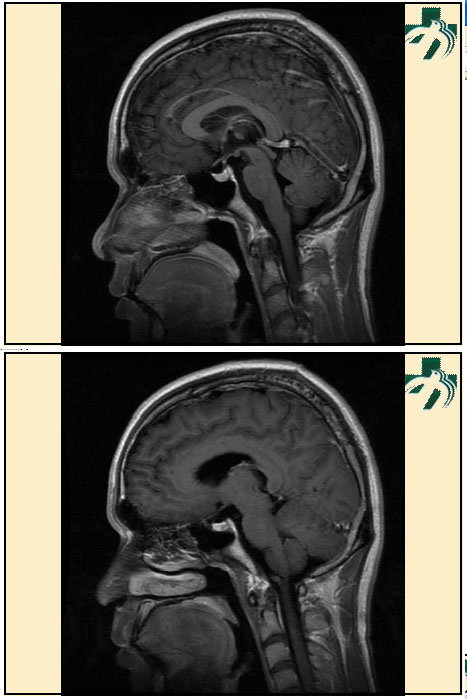

奴卡氏菌感染

第九期三博

读片会

病例之四

北京协和医院 提供

男性,22岁。自觉虫咬后皮疹、肢体麻木4月